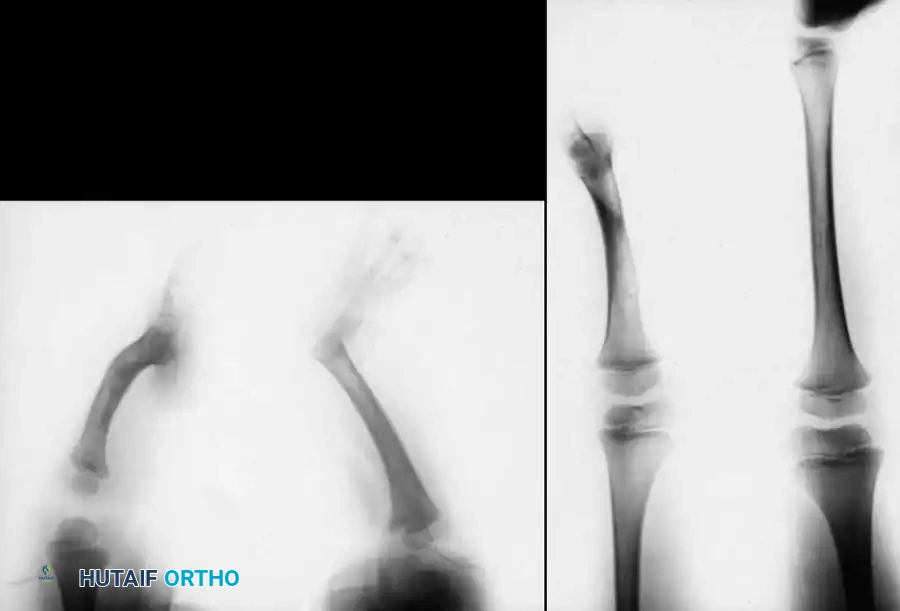

TIBIAL HEMIMELIA

Since the disorder was first described by Otto in 1941, tibial hemimelia has been known by a variety of names in the academic literature, including congenital longitudinal deficiency of the tibia, congenital dysplasia of the tibia, paraxial tibial hemimelia, tibial dysplasia, and congenital deficiency or absence of the tibia.

This condition represents a broad spectrum of deformities, ranging from the total absence of the tibia (the most severe form) to mild hypoplasia of the tibia (the least severe form). The incidence is exceedingly rare, estimated at one in 1 million live births, and the condition presents bilaterally in approximately 30% of affected patients.

Clinically, the involved leg is significantly shortened. The fibular head is often palpable, particularly if it is proximally displaced into the popliteal fossa. The foot is typically held in severe, rigid equinovarus, and the hindfoot is profoundly stiff.

In older children, the proximal tibial anlage may be palpable upon deep clinical examination, even if it is not radiographically visible. The knee is generally flexed, and in more severe deformities, profound quadriceps insufficiency causes an absolute lack of active knee extension.

Classification of Tibial Hemimelia

The most widely utilized and surgically relevant classification scheme for tibial hemimelia is that of Jones, Barnes, and Lloyd-Roberts. This system is based on early radiographic presentation and directly guides treatment recommendations.

- Type 1A Deformity: There is complete radiographic absence of the tibia and a hypoplastic distal femoral epiphysis compared with the contralateral normal side.

- Type 1B Deformity: There is no radiographic evidence of an ossified tibia; however, the distal femoral epiphysis appears more normal in size and shape. This distinction is critical because Type 1B deformities possess a proximal tibial cartilaginous anlage that can be expected to ossify over time. Modern imaging techniques, such as high-resolution ultrasound and MRI, are mandatory to identify this cartilaginous anlage.

- Type 2 Deformity: A proximal tibia of varying size is present and ossified at birth. The fibula is usually normal in size, but the fibular head is proximally dislocated.

- Type 3 Deformity: The proximal tibia is not radiographically visible, but the distal tibial epiphysis is present. This is an exceptionally rare variant. The distal femoral epiphysis is usually well-formed, but the upper end of the fibula is proximally dislocated, leading to profound knee instability.

- Type 4 Deformity: The tibia is shortened, and there is proximal migration of the fibula with distal tibiofibular diastasis. This rare deformity is also referred to as congenital diastasis of the ankle joint. The distal tibial epiphysis may be entirely absent.